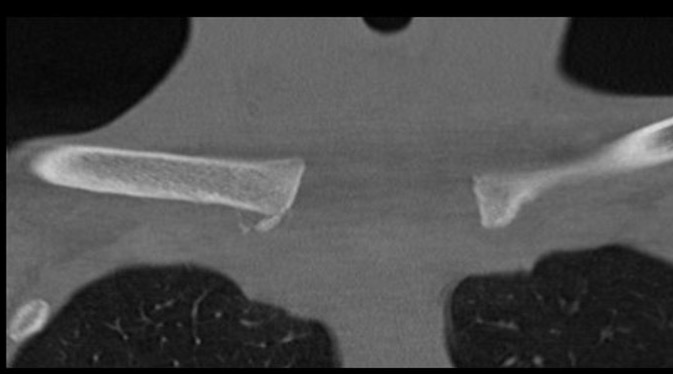

Condensing Osteitis

Definition

Sclerosis of the medial end of the clavicle

Does not affect the sternum

Xray

CT